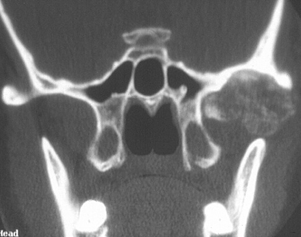

polyostotic fibrous dysplasia